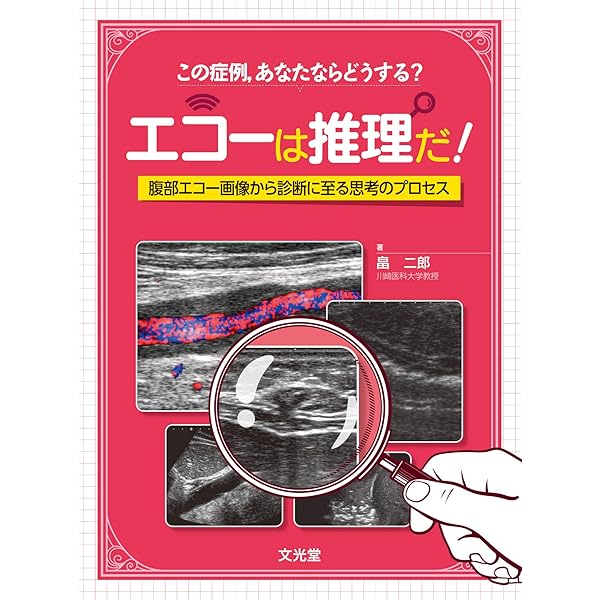

もらって嬉しい出産祝い 消化器内科 第28号(Vol.4 No.3,2022)特集:体外式超音波による 医学一般

もらって嬉しい出産祝い 消化器内科 第28号(Vol.4 No.3,2022)特集:体外式超音波による 医学一般

消化器内科 第28号(Vol.4 No.3,2022)特集:体外式超音波による,

消化器内科 第28号(Vol.4 No.3,2022)特集:体外式超音波による, 消化管エコーの最新動向 - 新。超音波診断 Vol.03 - 東芝,

消化管エコーの最新動向 - 新。超音波診断 Vol.03 - 東芝, 腹部超音波検査(腹部エコー検査) | 医療法人 木村医院,

腹部超音波検査(腹部エコー検査) | 医療法人 木村医院, 消化管エコーの最新動向 - 新。超音波診断 Vol.03 - 東芝,

消化管エコーの最新動向 - 新。超音波診断 Vol.03 - 東芝, 消化器内科 第18号(Vol.3 No.5,2021)特集:食道胃接合部癌の診断